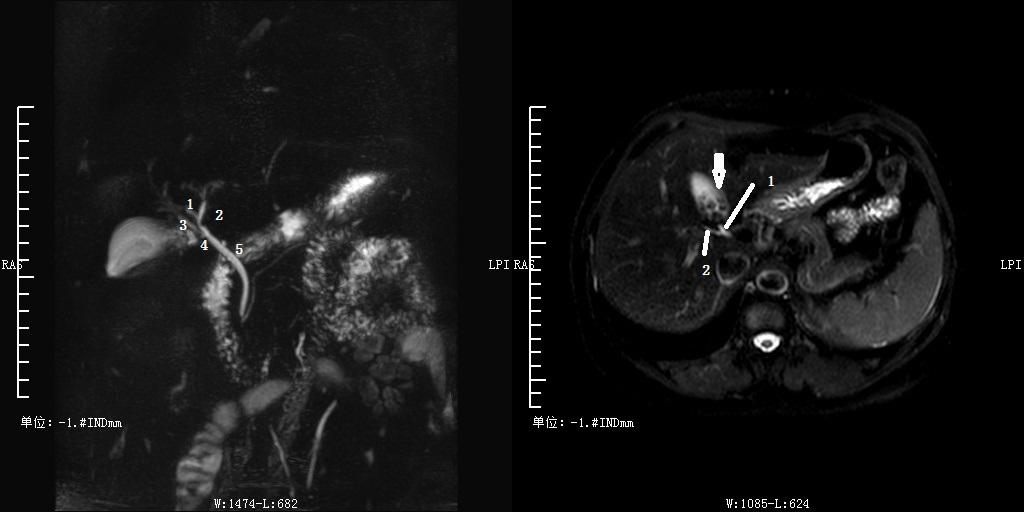

Ⅲa 型:右后肝管汇入左肝管。左图:1 为右前肝管,2 为右后肝管,3 为肝左管,4 为肝总管,5 为胆总管。

Ⅲb 型为右后肝管汇入肝总管。图 1 为右前肝管,2 为肝左管,3 为右后肝管,4 肝总管,5 胆囊管,6 胆总管。

Ⅲc 型为为右后肝管汇入胆囊管。左图 1 为右前肝管,2 为肝左管,3 为右后肝管,4 为胆囊管,5 为胆总管;右图 1 为胆囊管,2 为右后肝管,箭头为胆囊结石。